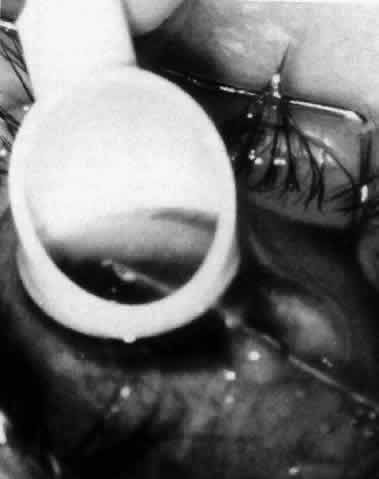

The variety of surgical procedures suggested by glaucoma specialists is adequate testimony to their lack of success. Filtering procedures have always been fraught with difficulty in all patients with inflammatory disease, but in younger patients the success rate is less than 50%. Trabeculectomy, peripheral iridectomy with thermal sclerostomy (advocated by Preziosa and Scheie), trabeculodialysis (advocated by Kanski; Fig. 2), and trabeculectomy with mitomycin have all failed to appreciably improve the prognosis of this complication.

Fig. 2. Intraoperative photograph of patient with inflammatory glaucoma undergoing trabeculodialysis. (Courtesy of Jack Kanski, MD)